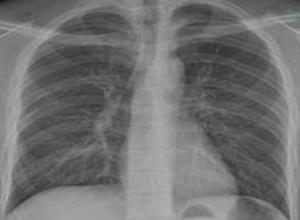

肺气肿x线

肺气肿x线,肺x线

肺气肿的影像诊断

肺气肿x线表现

肺气肿x线胸片特征

肺气肿的x线表现图片

肺气肿胸片典型图片